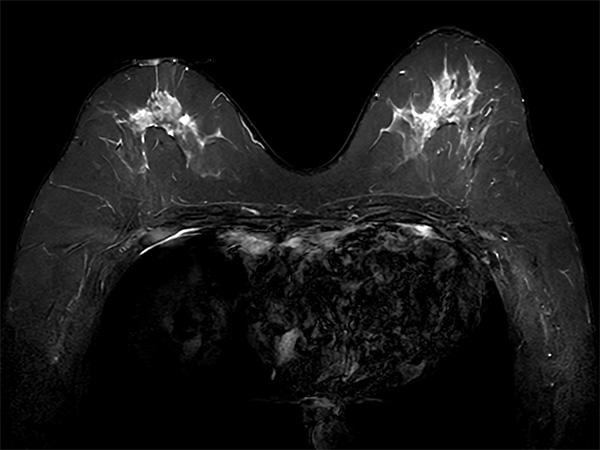

Axial STIR TSE